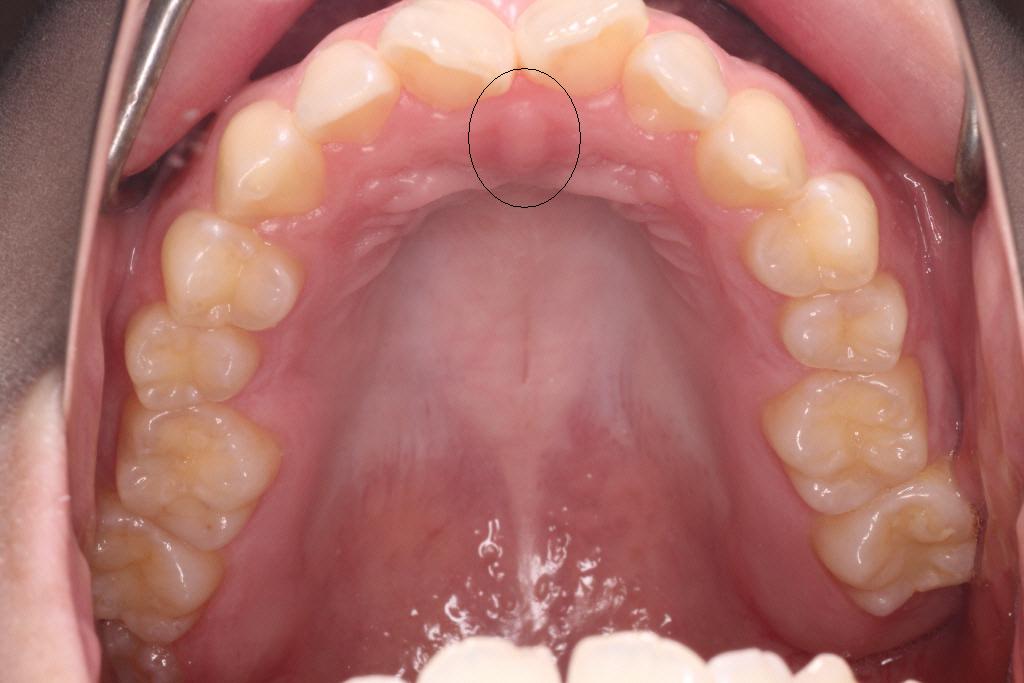

スポット(上の写真)は前歯の少し後ろのプクッとしている所に舌の先をつけ、舌全体を上あごにつけます。